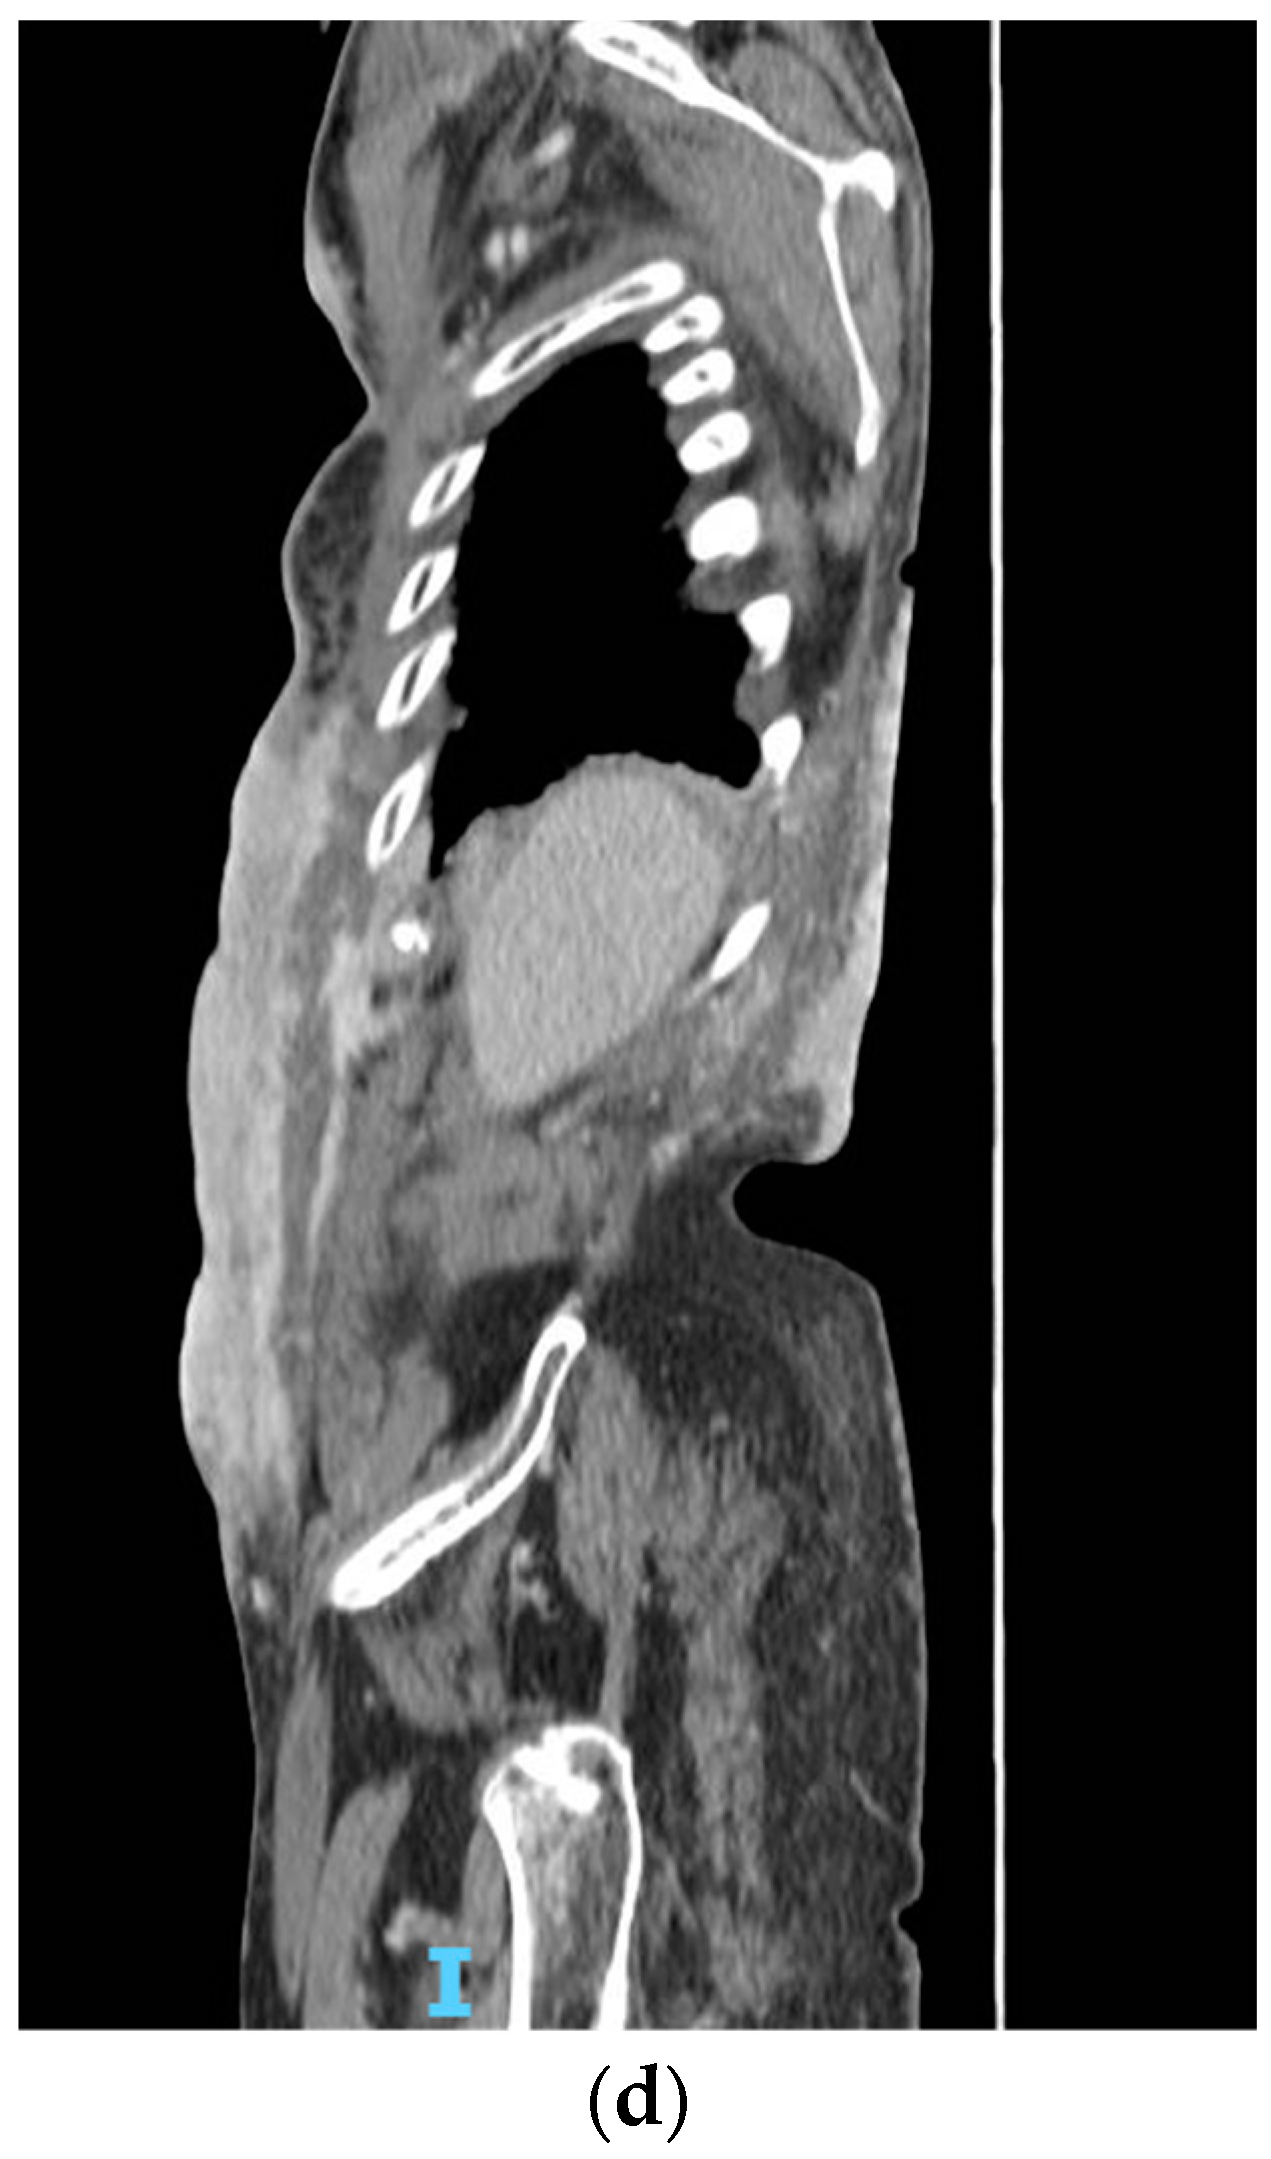

Figure 5.

(a,b) Clinical and (c,d) radiological disease progression in May 2022.